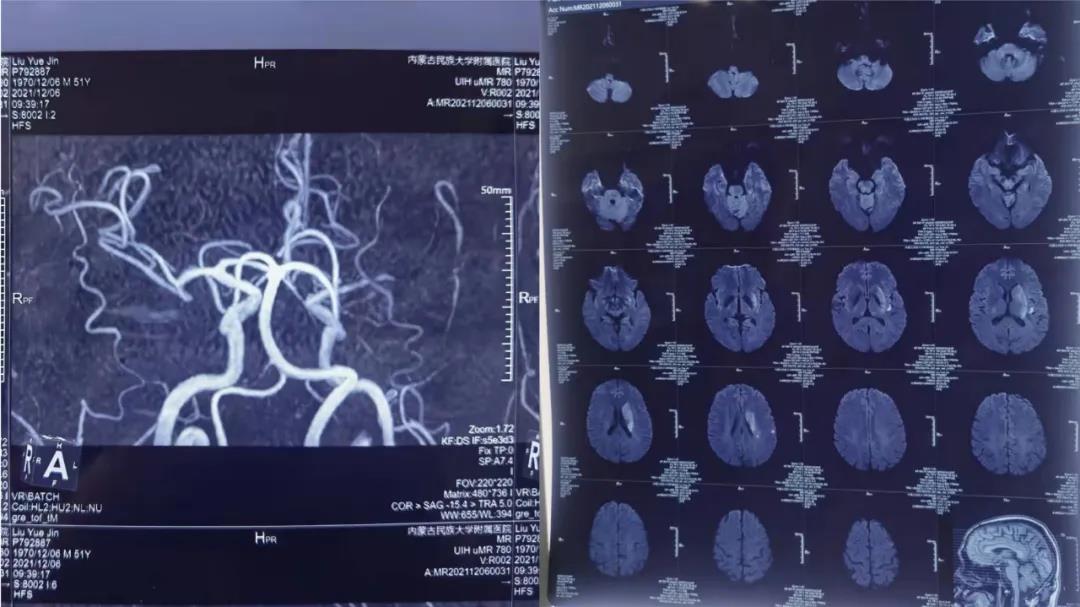

12月6日上午刘某在家休息,家属发现其睡眠增多,并且逐渐出现右侧肢体无力,上肢不能拿东西,下肢不能站立行走等症状,家人紧急将患者送入附近的一家医院进行救治,经过头CT、头MRI检查后诊断“急性脑梗死、左侧大脑中动脉闭塞”,该医院立即给予患者尿激酶静脉溶栓治疗,但溶栓后患者右侧肢体无力症状仍未得到改善。患者家属随即联系了我院,我院卒中中心分管副院长杜艳秋、介入组组长徐鹏评估后,其NIHSS评分16分考虑有急诊手术指征,建议立即行“颅内动脉取栓术”,时间就是大脑,时间就是生命,患者到达我院后,卒中中心迅速启动了绿色通道,以最快的速度完成术前准备,一场挽救生命的战争正悄无声息地展开,从入院到穿刺成功只用了10分钟,经过30分钟的取栓后,终于可见血流清晰通过。至此,生命的通道被重新开通,患者在手术台上,不但恢复了意识,完全瘫痪的右侧上下肢也能抬起了,从死神手中抢回一条生命,避免发生残疾,挽救了一个家庭!患者家属十分感激,特意为我院医务人员送来锦旗,深情致谢。

目前患者在神经内三科全体医护人员的精心照护下,肢体无力、言语混乱、嗜睡等症状基本消失,(NIHSS评分由入院的16分变为0分),很快可以康复出院。